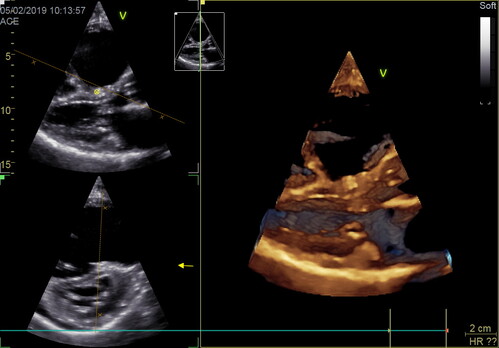

Каждый специалист эхокардиографии сталкивается в своей практике с этой группой больных на приеме. Это больные с дилатацией правых камер сердца различной этиологии.

Мы постараемся освятить все возможные причины, приводящие к дилатации отдельно легочной артерии, правого желудочка, правого предсердия и всех их вместе взятых.

Лекция посвящена диагностике врожденных и приобретенных шунтов различной этиологии.

Речь пойдет и о врожденных и о приобретенных шунтах. Это и дефекты перегородок, и открытый артериальный проток, и коронарные фистулы, и разрывы миокарда, и разрывы абсцесса корня аорты.

Помимо этого, мы обсудим диагностику открытого овального окна. Особую важность приобретает диагностика приобретенных шунтов, поскольку они требуют хирургической коррекции в связи с тяжелым нарушением гемодинамики. Все это требует детальной проработки и системного подхода.